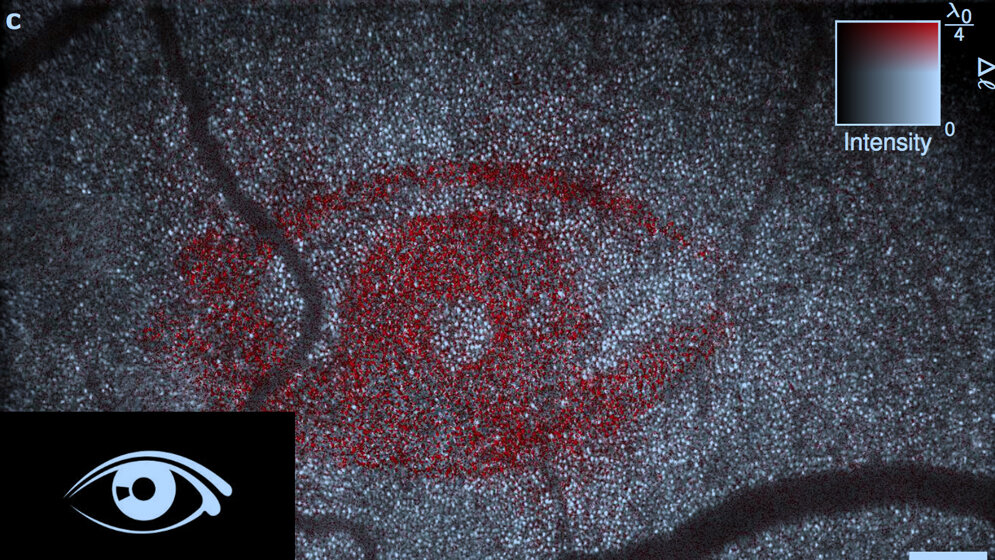

Der Arbeitsgruppe von Gereon Hüttmann, Institut für Biomedizinische Optik, und Dierck Hillmann, OCT-Forschung der Thorlabs GmbH, gelang es nur mit Hilfe numerischer Korrekturverfahren, unvermeidliche Bildfehler des Auges zu korrigieren und so einzelne Photorezeptoren sichtbar zu machen. Anschließend konnten sie auch deren Funktion detektieren: Sie beobachteten im Menschen, dass sich die Photorezeptoren bei Stimulation durch Licht um wenige Nanometer ausdehnten. Dies ist ein wichtiger Schritt auf dem Weg, die primären Sehvorgänge in den Photorezeptoren quantitativ zu vermessen.

Die Lübecker Forscher setzten ein neuartiges, selbst entwickeltes OCT-Verfahren ein. Statt die Netzhaut mit einem fokussierten Laserstrahl abzutasten, bildet dieses ein wenige Millimeter großes Feld auf einer Hochgeschwindigkeitskamera ab. Mit dem Gerät wird nicht nur die Stärke, sondern auch die Laufzeit des Lichtes mit bisher kaum möglicher Präzision bestimmt. So konnten die Forscher messen, wie sich die Zeit verändert, die das Licht braucht, um die Photorezeptoren zu passieren - und damit auf mögliche Änderungen in der Dicke der Photorezeptorzellen mit Nanometergenauigkeit zurückschließen. Das verwendete Verfahren basiert auf dem in Lübeck entwickelten Prinzip der Holoskopie, das bereits mit zwei Preisen ausgezeichnet wurde.

Mit dieser Technik wurde ein bisher von vielen internationalen Gruppen vergeblich verfolgtes Ziel erreicht – funktionelle Messungen an einzelnen Sehzellen im Menschen. Damit ergeben sich neue diagnostische Möglichkeiten, die es jetzt zu evaluieren gilt. Aber auch das Verständnis der dem Sehvorgang zugrunde liegenden Mechanismen und die Entwicklung innovativer Therapiemöglichkeiten wie Gen- und Stammzelltherapie mögen entscheidend von dieser nicht-invasiven, funktionellen Messung profitieren.